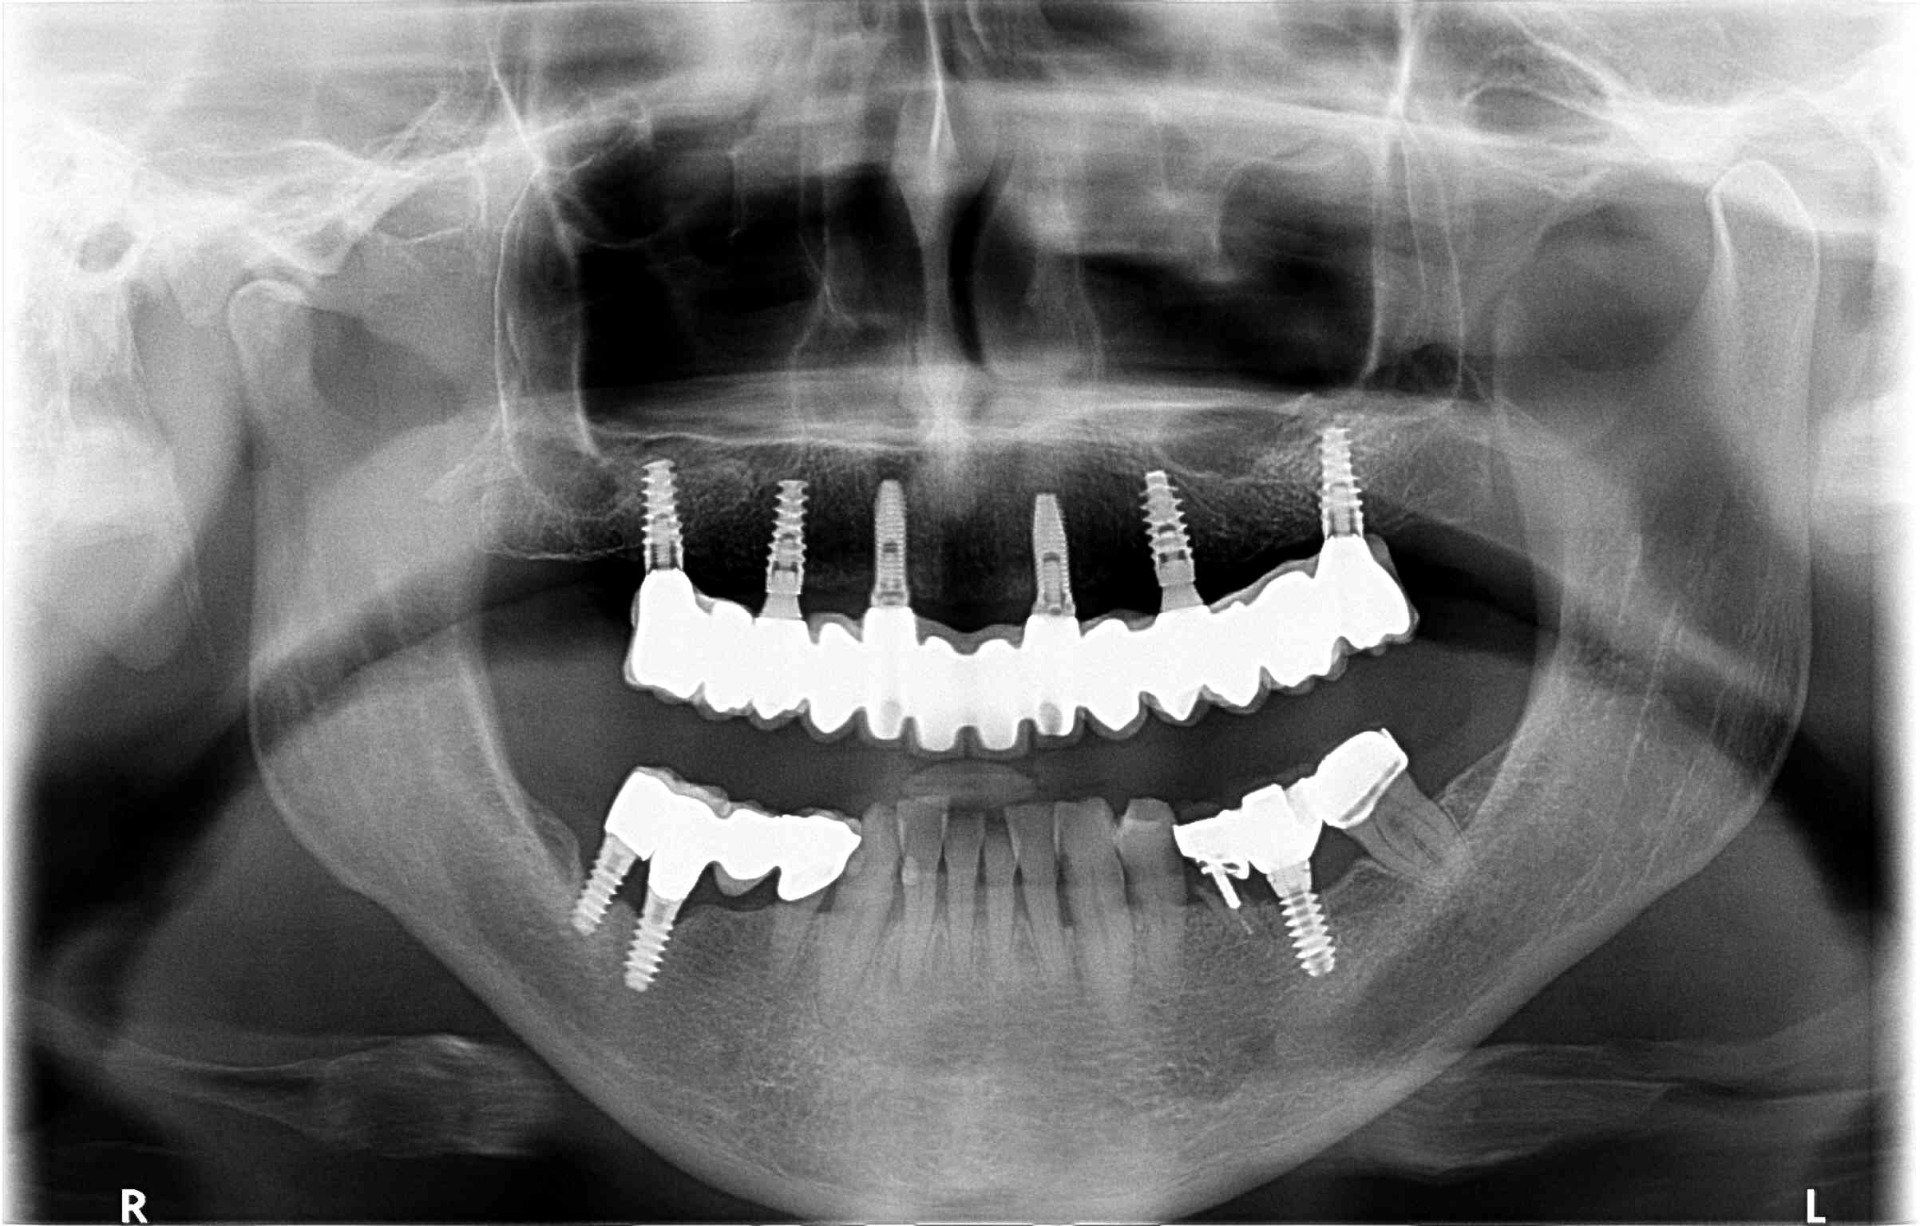

La implantología es la especialidad odontológica que se ocupa de la sustitución de la raíz del diente perdido.

La sustitución se hace mediante una pequeña intervención quirúrgica para colocar una pieza de titanio dentro del hueso maxilar.

El implante tiene una rosca en su interior donde posteriormente se enroscará el pilar que soportará la corona protética.

Después de la valoración del implantólogo y un diagnóstico muy esmerado por parte del equipo profesional se plantean diferentes soluciones. Dependiendo del problema planteado que puede ser: pérdida unitaria, pérdida múltiple o desdentado completo...se realizará la técnica precisa con el fin de mejorar la calidad de vida del paciente.

El Centre Odontològic Piñera dispone de un equipo radiológico de última generación que permite hacer Ortopantomografias (radiografías de toda la boca), CBCT dental y escáner dental intraoral en 3D (3 dimensiones). La exposición radiológica es mínima.

Esta tecnología favorece la rapidez en la exploración, así como la precisión en el diagnóstico y el consiguiente tratamiento.